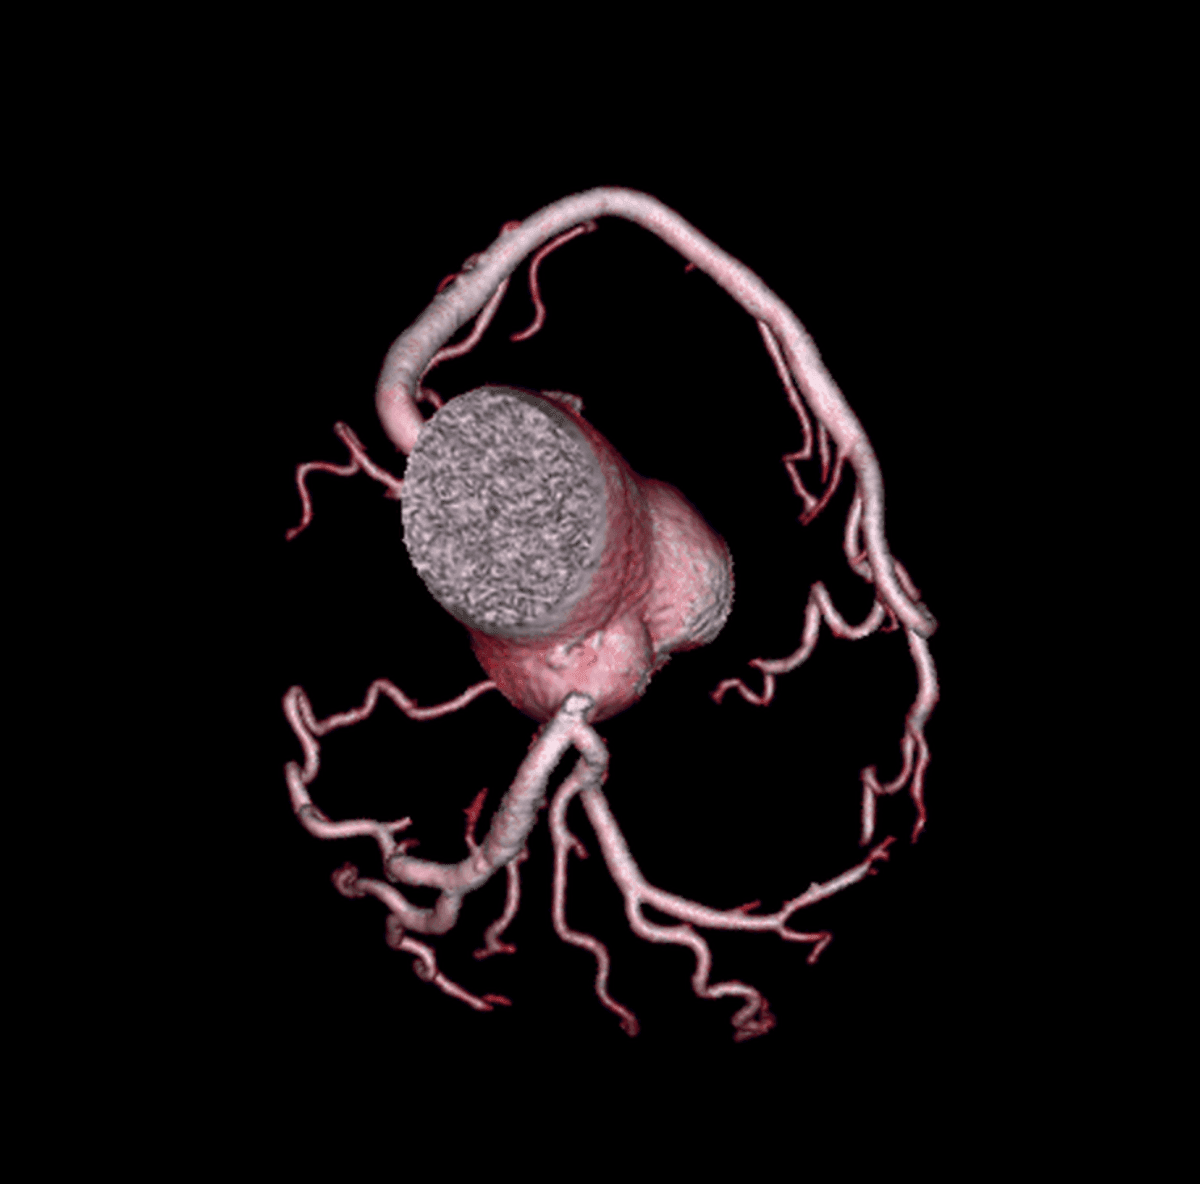

A angiotomografia de coronárias (ATC) mostrou grandes avanços tecnológicos nas últimas 2 décadas. Nos dias atuais, pacientes com suspeita de DAC obstrutiva com baixo/intermediário risco cardiovascular…